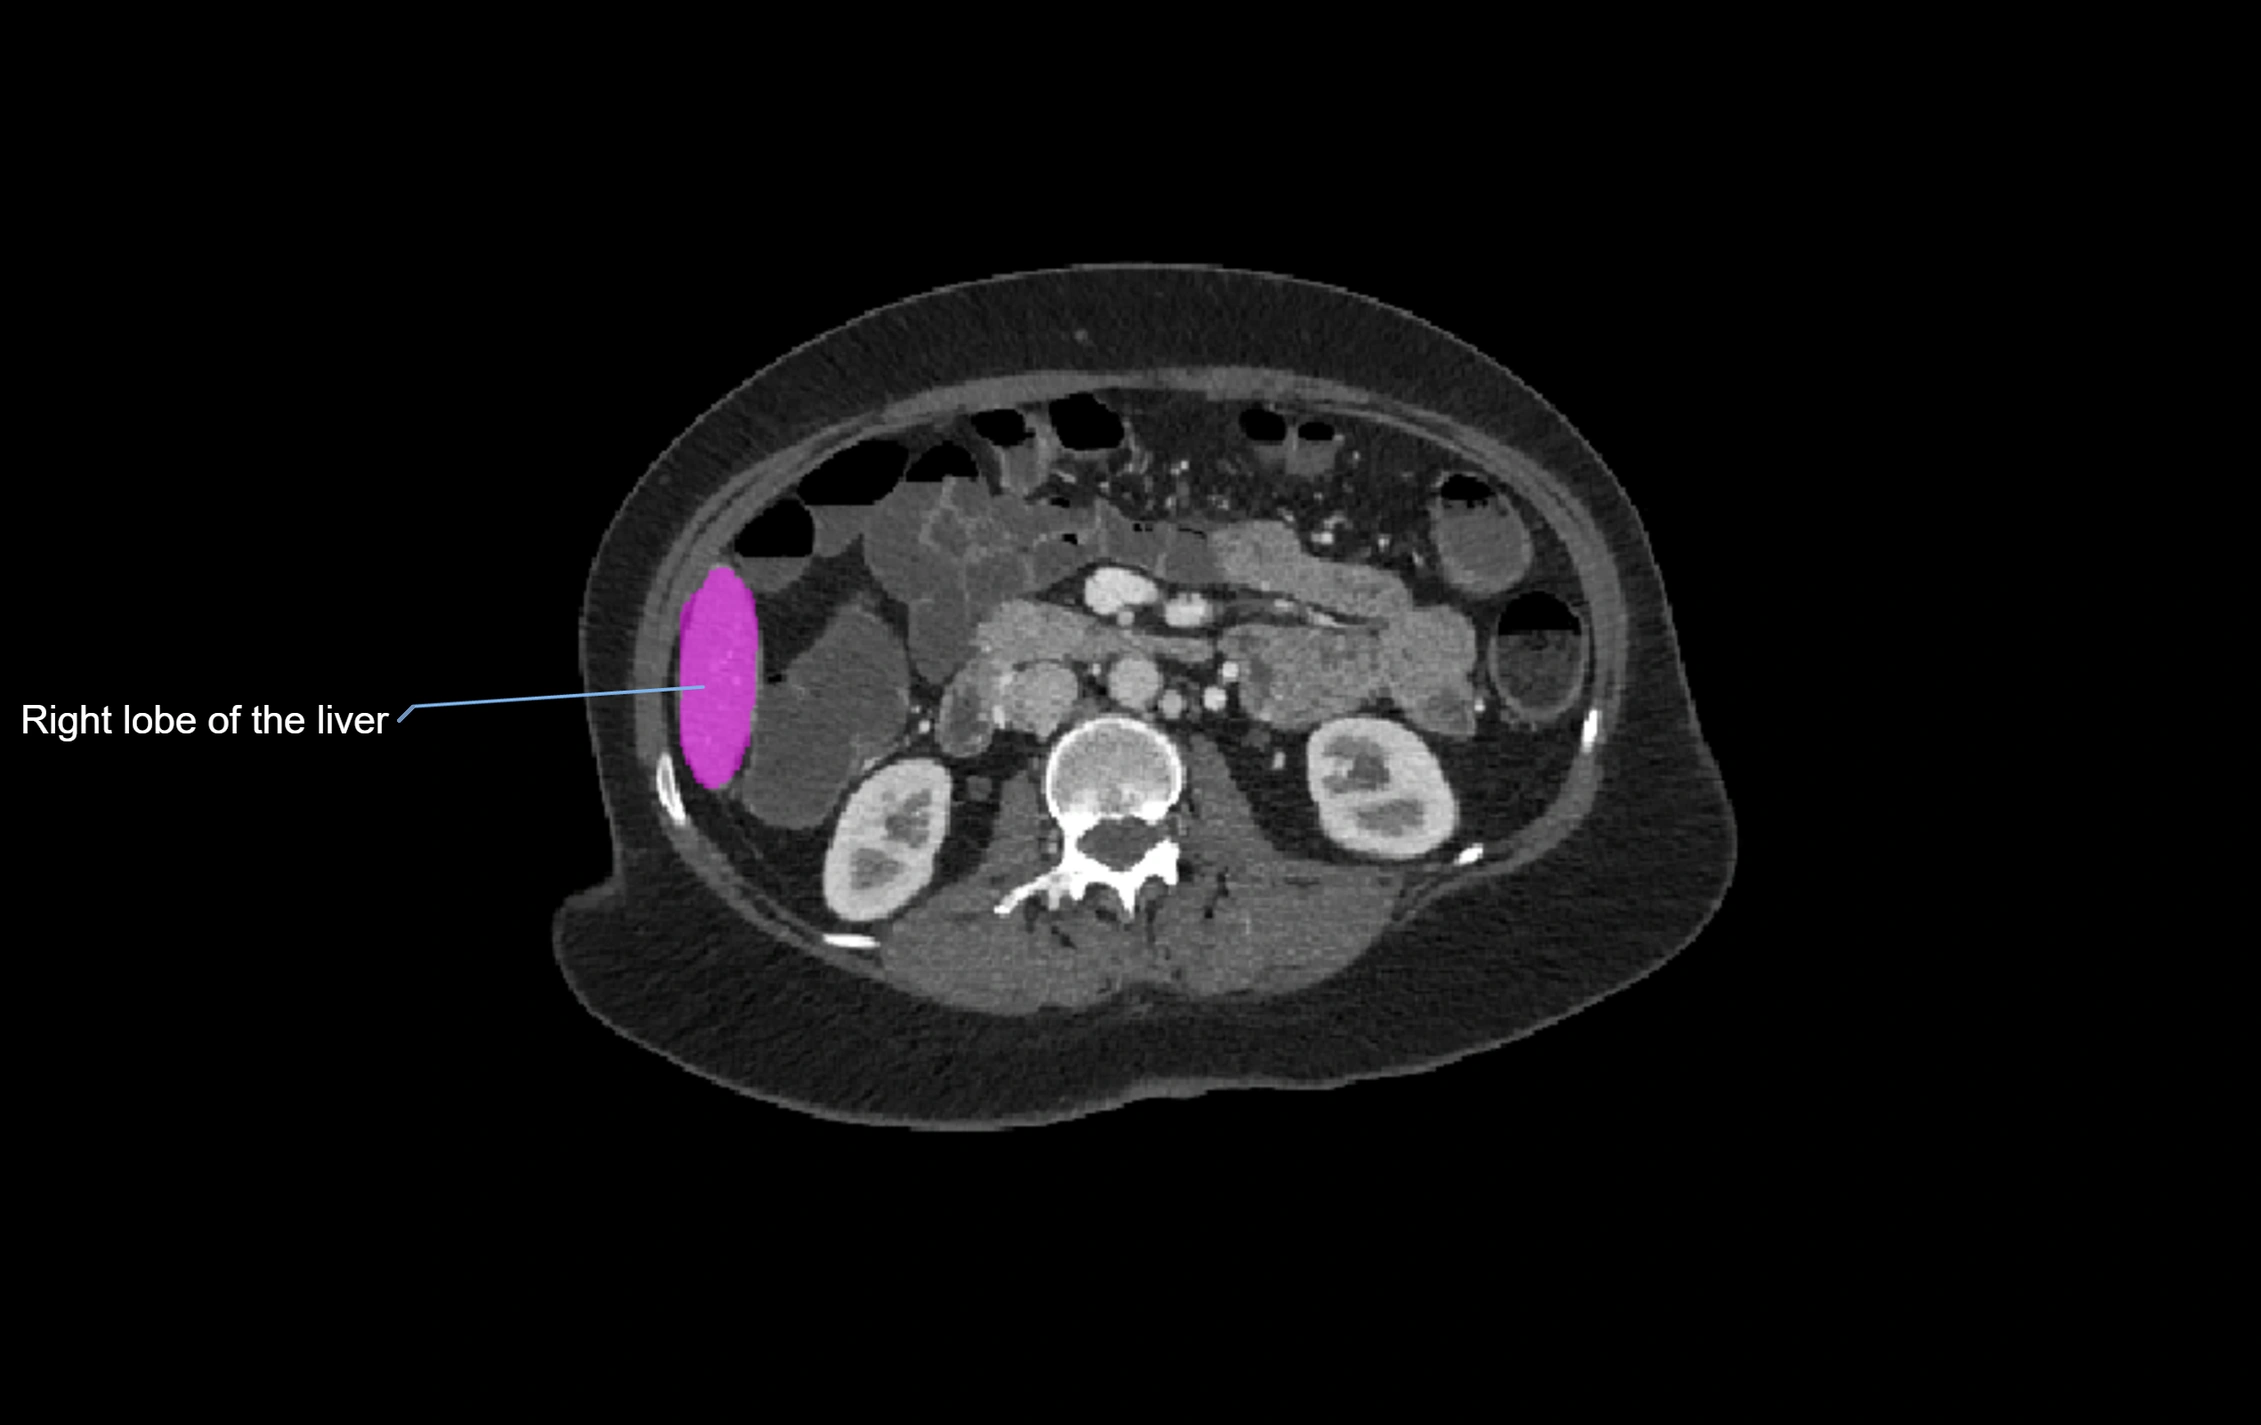

CT Image

image